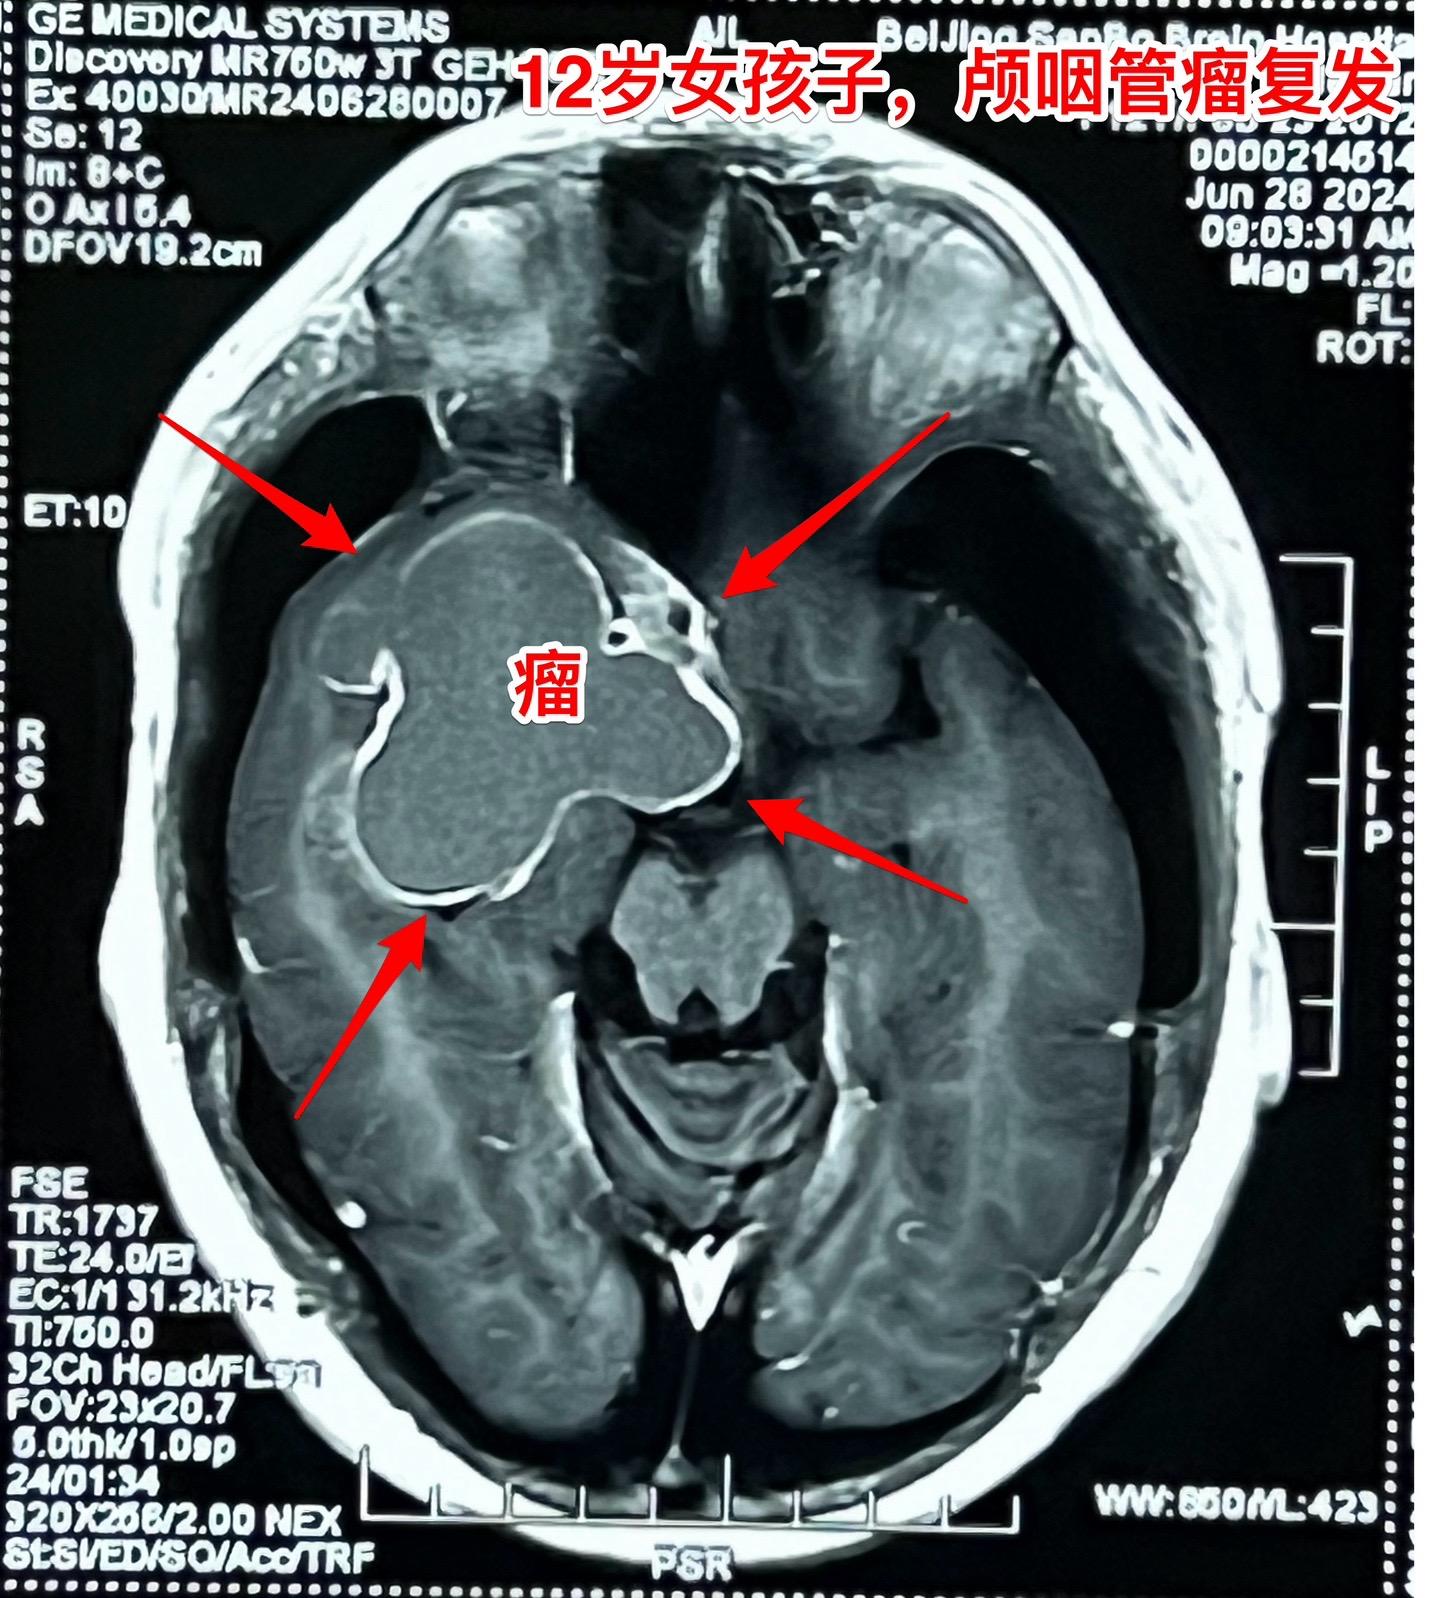

开颅手术+2次伽马刀治疗后颅咽管瘤复发。12岁的四川女孩子,5年前发现颅咽管瘤,在上海作过一次开颅手术,因颅咽管瘤残留先后作了两次伽马刀治疗。到三博脑科医院就诊时右眼已经失明了。 这样的颅咽管瘤属于难题中的难题! 肿瘤在增大,尽管切除肿瘤的难度大,我们不应该放弃,而是要积极再次手术,争取将肿瘤完全切除。 2024年7月2日作了开颅手术,将巨大肿瘤完全切除。